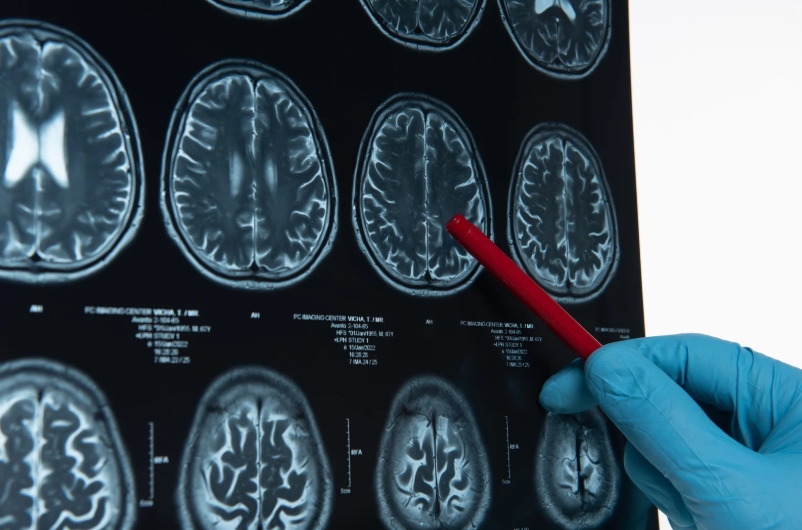

또한, 의식이 혼미해지거나 말이 어눌해지고, 상대방의 말을 이해하지 못하는 등 의사소통에 문제가 생길 수 있습니다. 이런 변화는 뇌출혈 부위에 따라 다르게 나타날 수 있으며, 뇌간이나 대뇌피질 등 중요 부위에서 출혈이 발생할 경우 더욱 빠르고 심각한 증상으로 이어집니다. 특히 가족이나 주변인이 환자의 말투나 행동이 이상하다고 느꼈다면 즉시 병원으로 이송해야 합니다. 이른 시간 내에 뇌 CT나 MRI를 통해 정확한 진단을 받는 것이 예후에 결정적인 영향을 미칩니다.